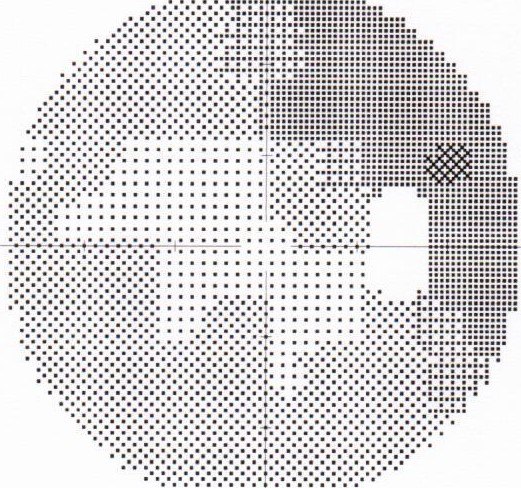

术前冠状位CT示: